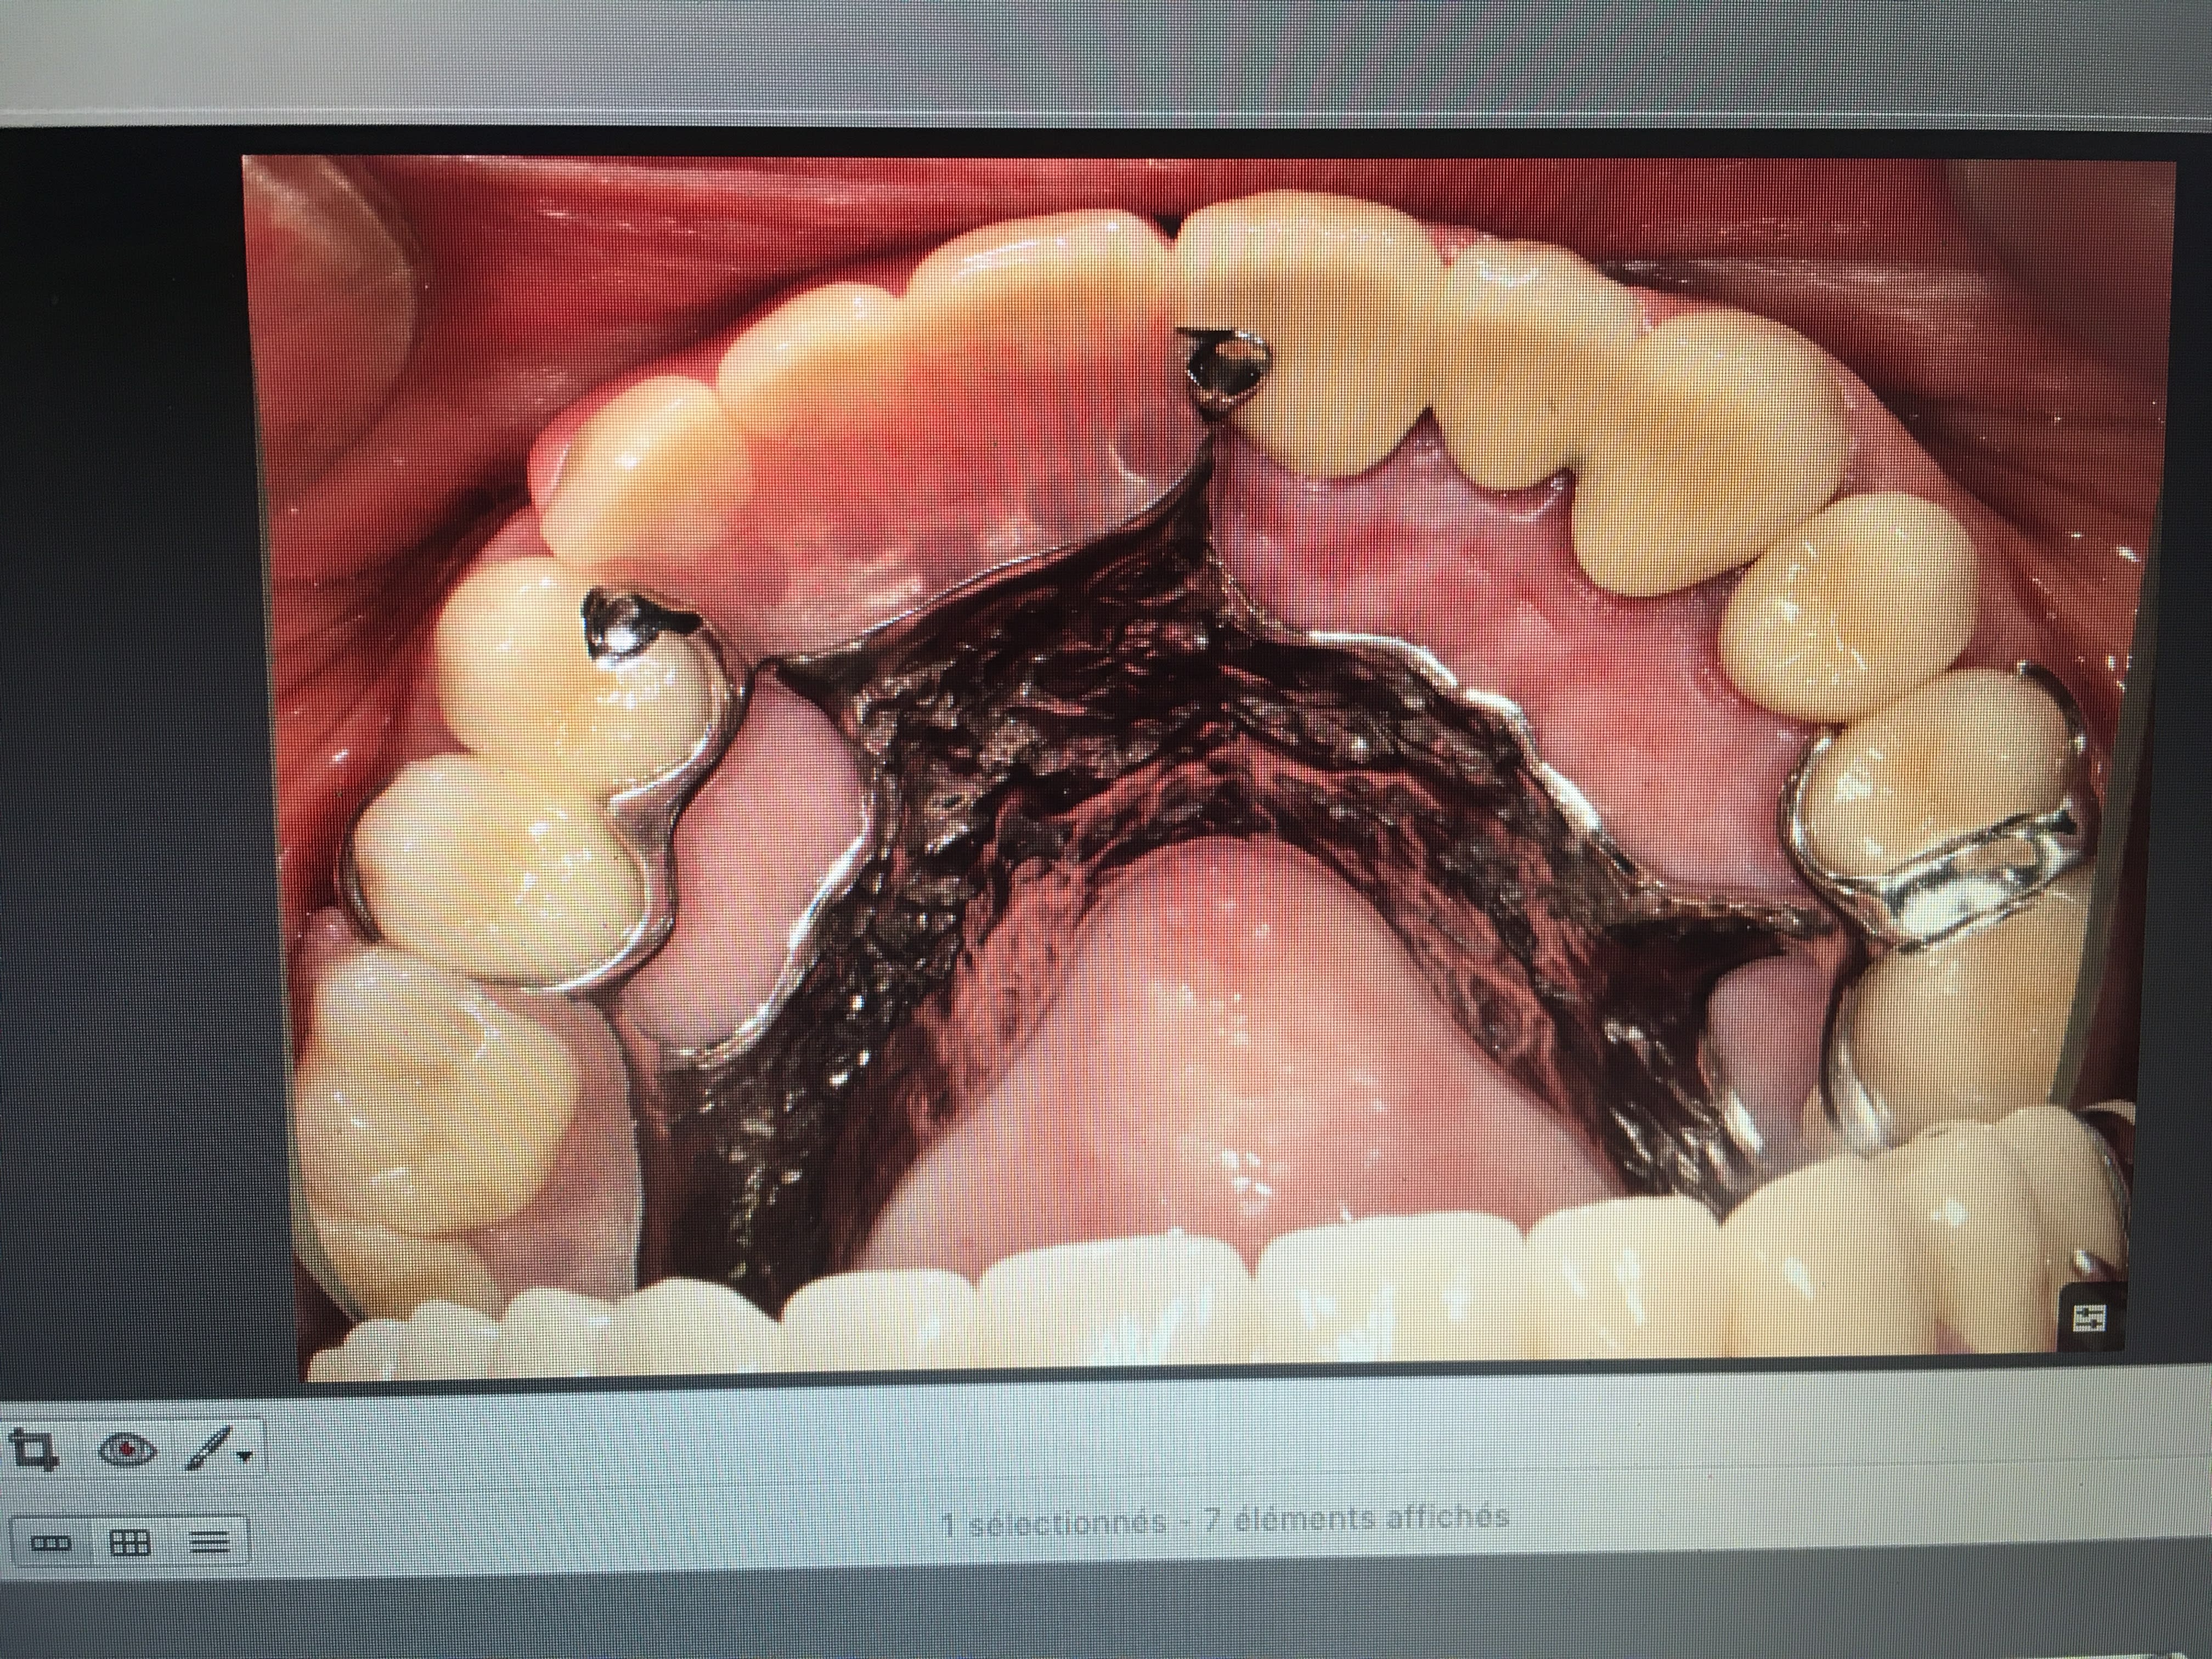

IC ceram 23 + stellite.

Plus longtemps que les dents restantes de l'autre coté. La patiente ne voulait pas passer au complet. Elle est au courant. Et passage au complet meme topo. One shot je me servirais de cette 23 comme base de réaccrochage de la camera. Ca s'appelle de l'efficience au sein d'un système de santé collectiviste. -)))

faire un stellite de grande portée associé à de la fixe ç est un enfer .

ç est la prothese de tres loin la plus intellectuelle .

pcq on la fait à l envers , tout simplement :-)) eh oui ,on a pas le choix en travail classique :-)

il faudrait pouvoir commencer par le stellite

( puisque ç est lui qui te donne la RIM +le volume de l arcade dentaire etc )

et mettre ensuite , les couronnes dans les espaces disponibles .

or ce n est pas possible pcq le stellite dépend des couronnes .

donc il faut pouvoir conceptualiser virtuellement le truc final , en démonter mentalement les séquences , pour pouvoir démarrer à l envers finalement .